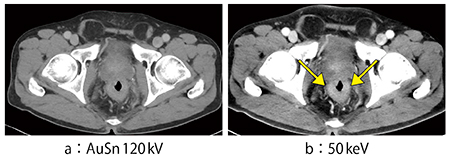

症例2は,HCCにてTACEを繰り返し行っている症例である。AuSn120kV画像では,再発が1か所と,淡い濃染像が1か所確認できるが,そのほかは不明である。しかし,50keV画像では,S5に明瞭な濃染と,S2,S3に淡い濃染が認められ,さらには肝実質も均一に染まっていないことがわかる(図3)。50keV画像により,従来は見えていなかった病変も確実に拾い上げられるようになったという印象である。

図3 症例2:HCCにてTACEを繰り返し行っている症例